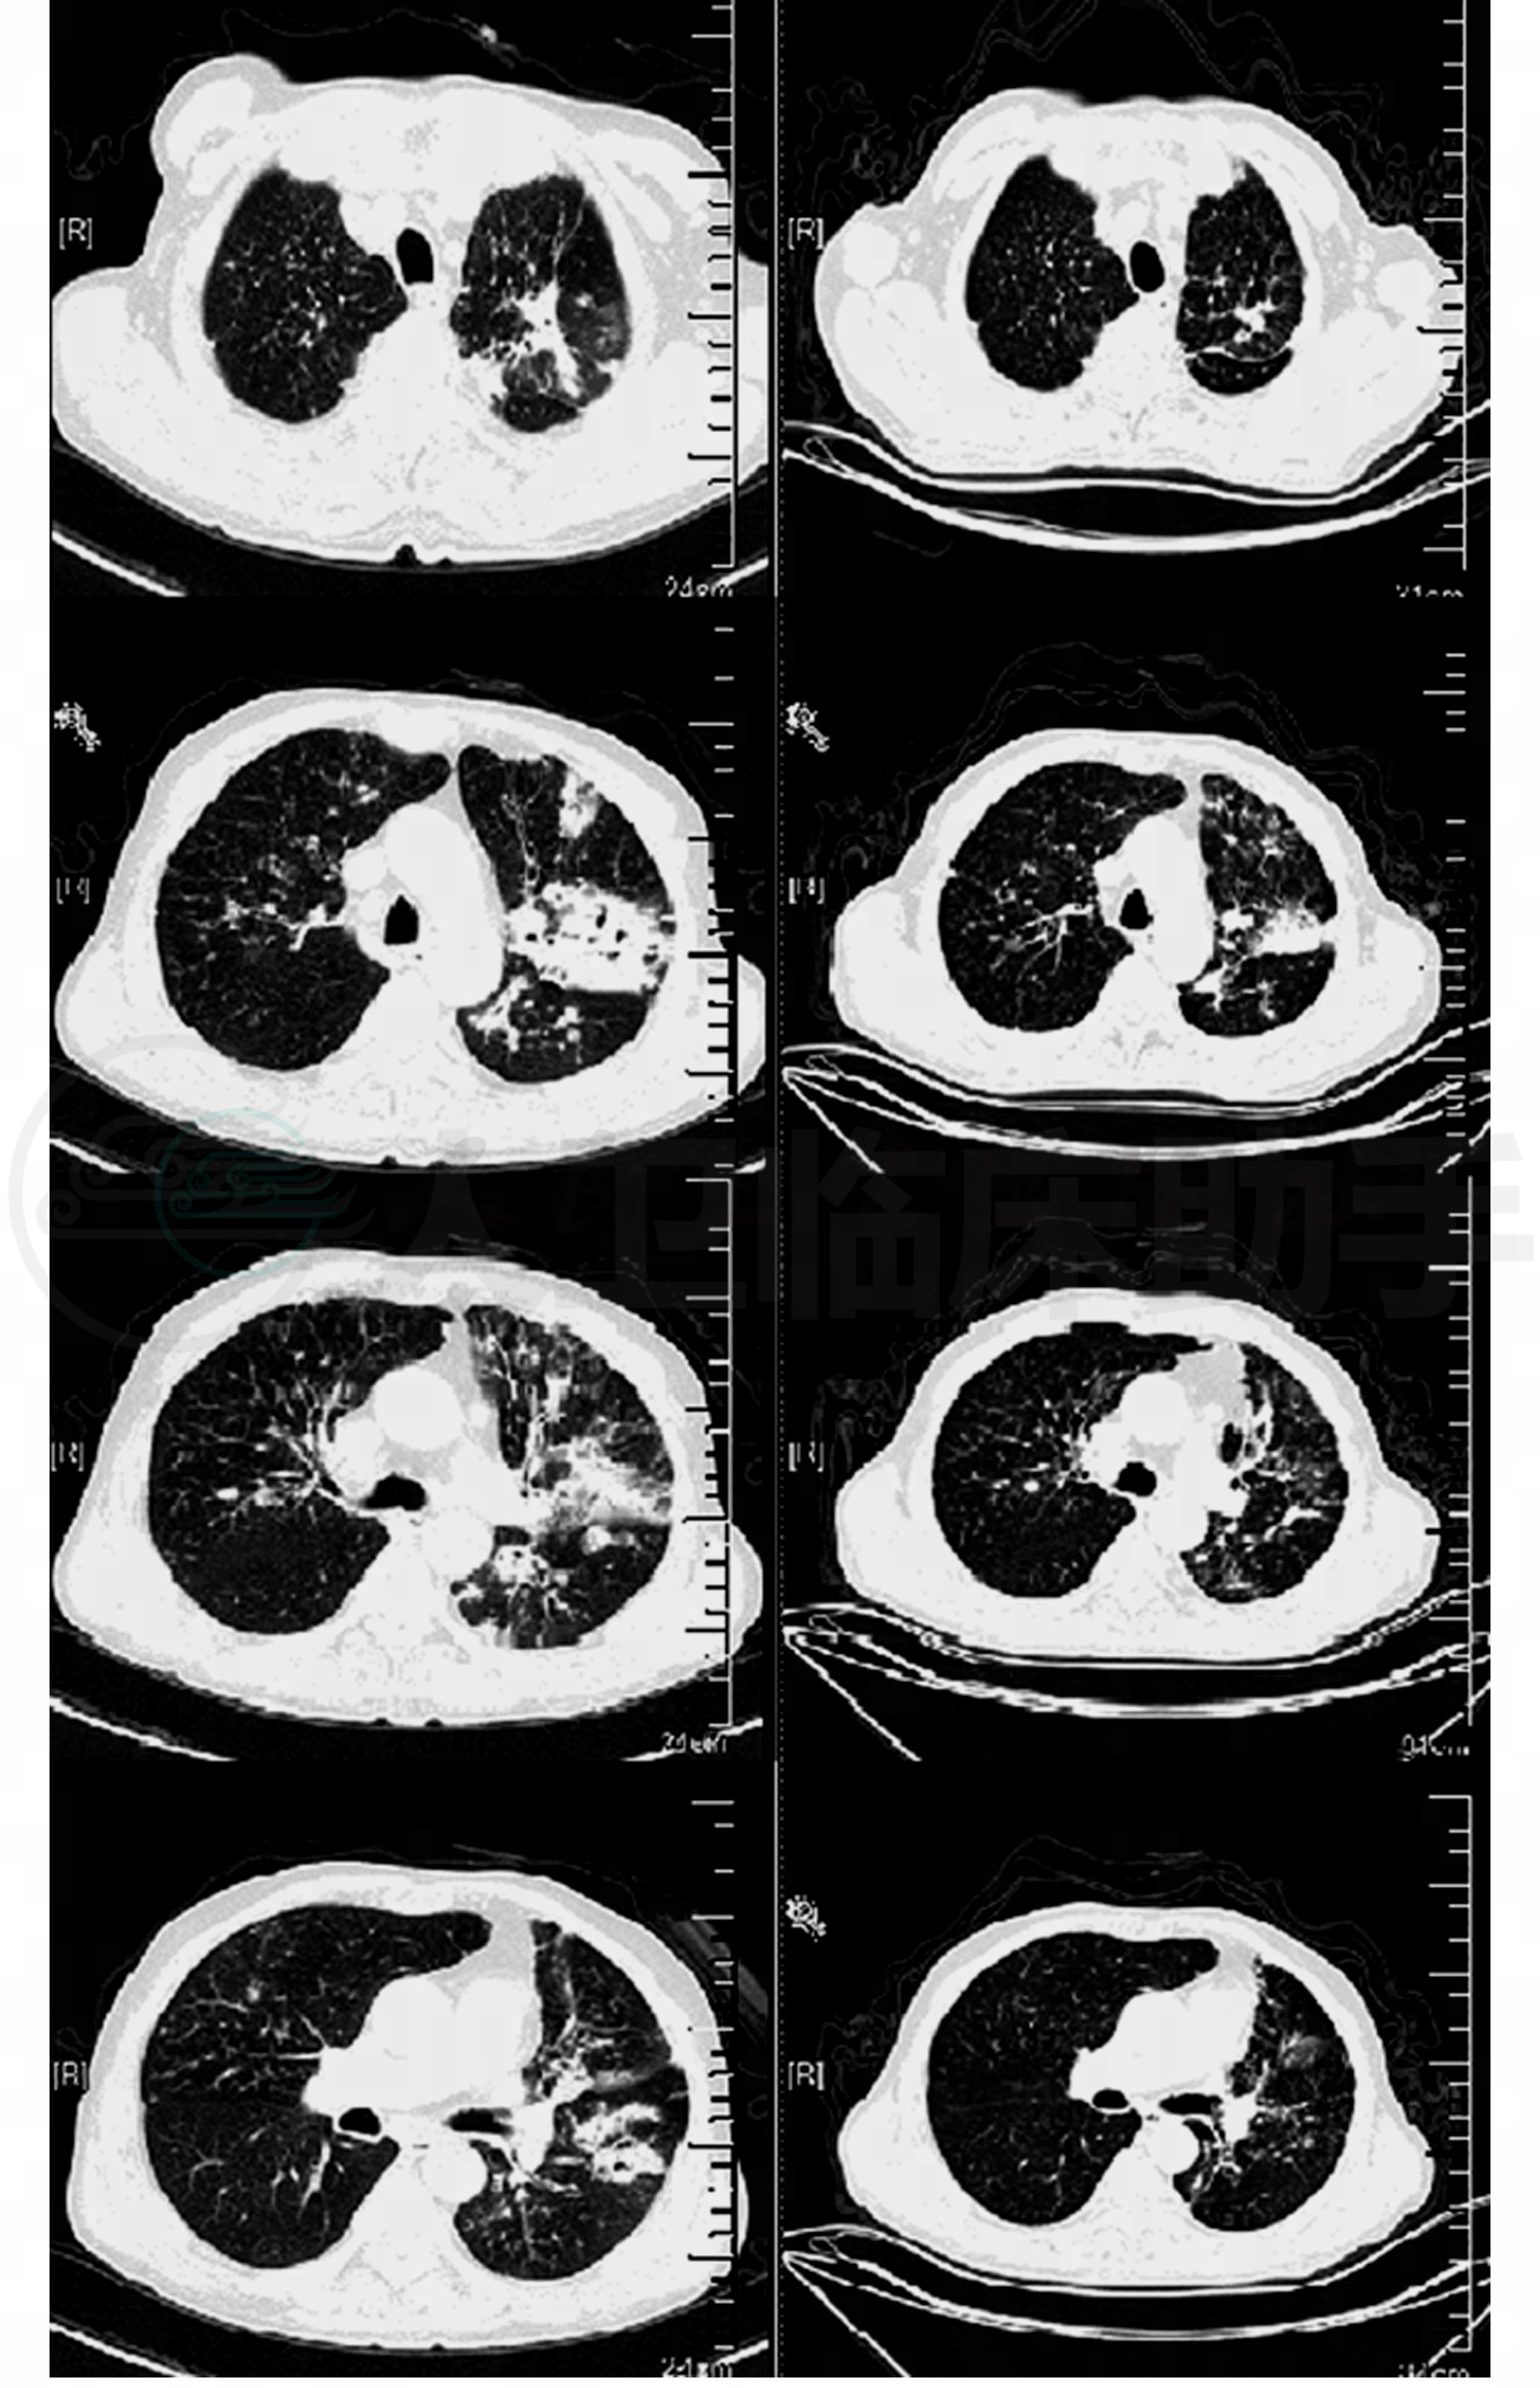

再次入院辅助检查:血常规:白细胞23.0×109/L,中性粒细胞百分比87.3%,嗜酸性粒细胞百分比2.3%。复查肺CT(图2):肺部影像在前次肺部病变的基础上,斑片影扩大和实变,实变影内可见透光,另有新发浸润渗出病变;扩张的支气管的管壁增厚,周围渗出病变;左肺上叶病灶扩大。

图2 左图为首次入院,右图为再次入院。在前次肺部病变的基础上,斑片影扩大和实变,实变影内可见透光,另有新发浸润渗出病变;扩张的支气管的管壁增厚,周围渗出病变;左肺上叶病灶扩大